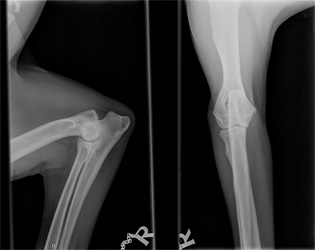

Norpan kinnerten ja kyynärten röntgenkuvat

Norpan jalkavaivoista tai yleensä OCD:sta kiinnostuneet voivat vilkaista alla olevia kuvia. Kuvat on otettu ajalta ennen kinnerten tähystystä ja ne saa suuremmaksi klikkaamalla. Lisäsin linkkien takaa löytyviin kinnerkuviin muutamia huomioita, jotka jäivät Esa Eskeliseltä ja Kai Skutnabbilta haetuista lausunnoista mieleen. En osaa itse tulkita röntgenkuvia, joten toivottavasti muistini ei reistaillut noita yksityiskohtia merkkaillessa. Kyynärkuvista jätin huomiot pois, koska en osaa osoittaa vasemmasta kyynärästä riittävän tarkasti sitä kohtaa, jossa Skutin mukaan on vähäisiä reaktioita havaittavissa. Eskelinen suositteli lausunnossaan myös kyynärnivelten tähystämistä, mutta Skutin mukaan oikea kyynärnivel on puhdas eivätkä vasemmankaan reaktiot viittaa OCD:hen.

Kyynärnivelet